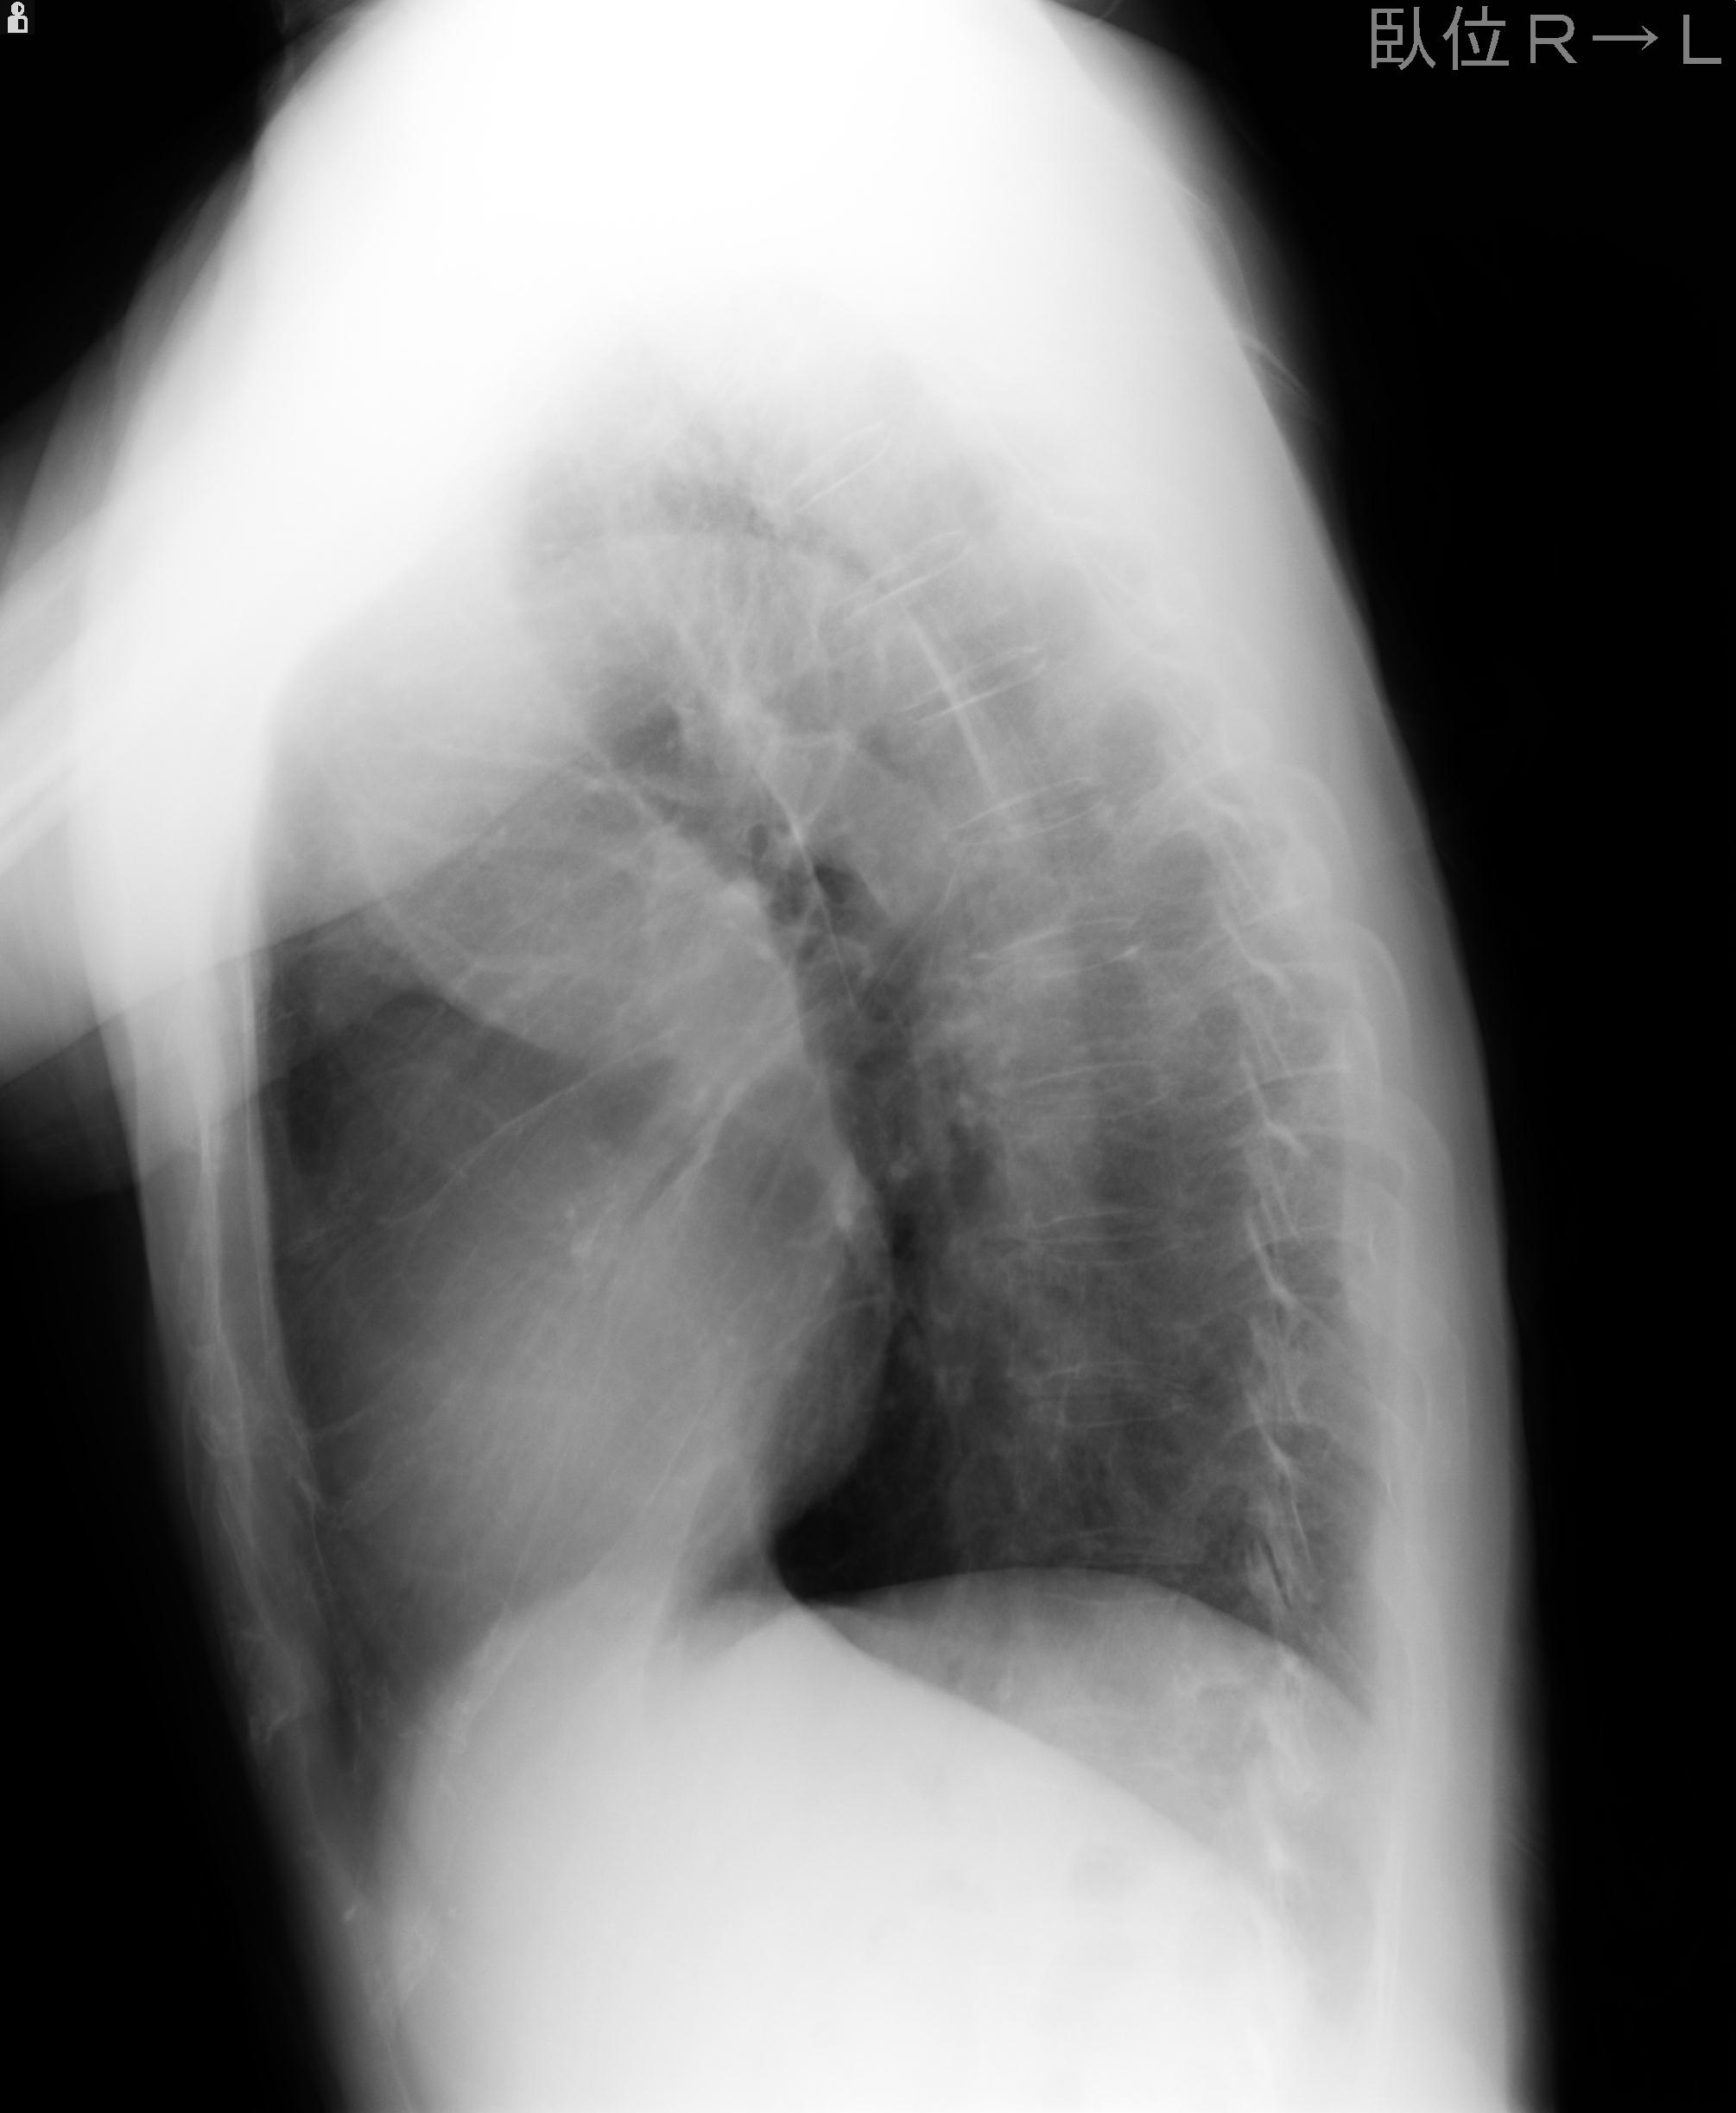

60058 3/9 11/4 右肩 2R+MRI 73歳男性 肩腱板損傷